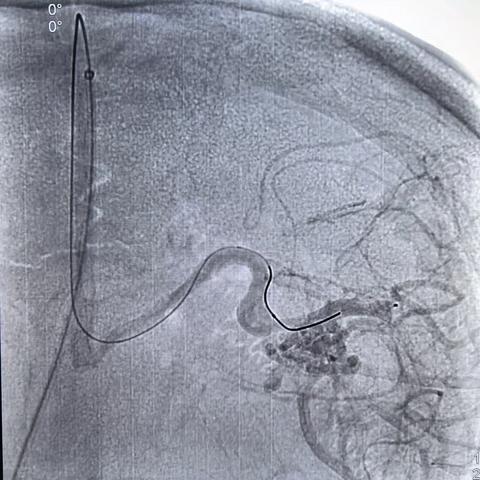

徐建国,男,45岁,额叶动静脉畸形-动静脉入路

01-26 264阅读